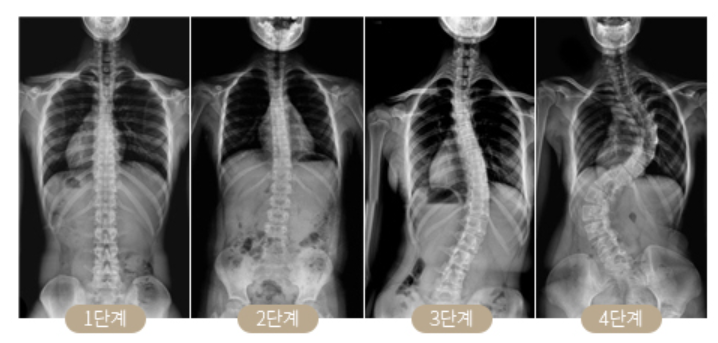

발바닥 굳은살 원인 5. 척추측만증

발바닥 굳은살 원인 다섯 번째는 척추측만증입니다. 특히 굳은살이 한쪽 발에만있다면 이는 척추측만증을 의심해봐야하는데 한쪽 발에만 있다는 것을 의미합니다. 이는 척추가 정상적이지않고 굽거나 휘어진것을 뜻하며 걸을때마다 체중을 두 다리에 골고루 분산시키지않기 때문에 한쪽 다리에만 발바닥 굳은살 원인이되기 때문에 방치해두면 각종 관절 질환에 걸리기 쉬우니 반드시 치료해야합니다.